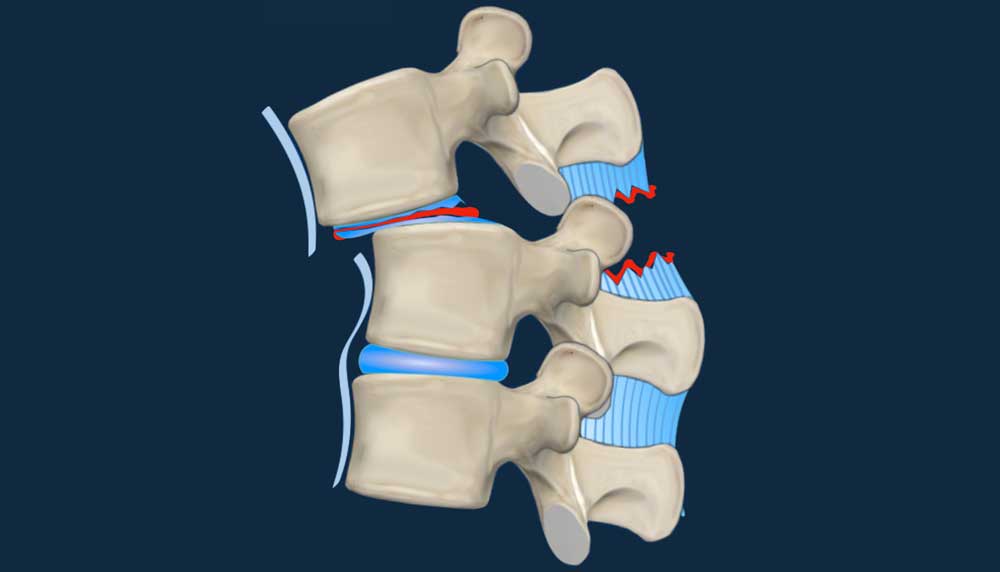

AO Spine Classification of Thoracolumbar Fractures

AO Spine Classification

Lecture by Frank Smithuis